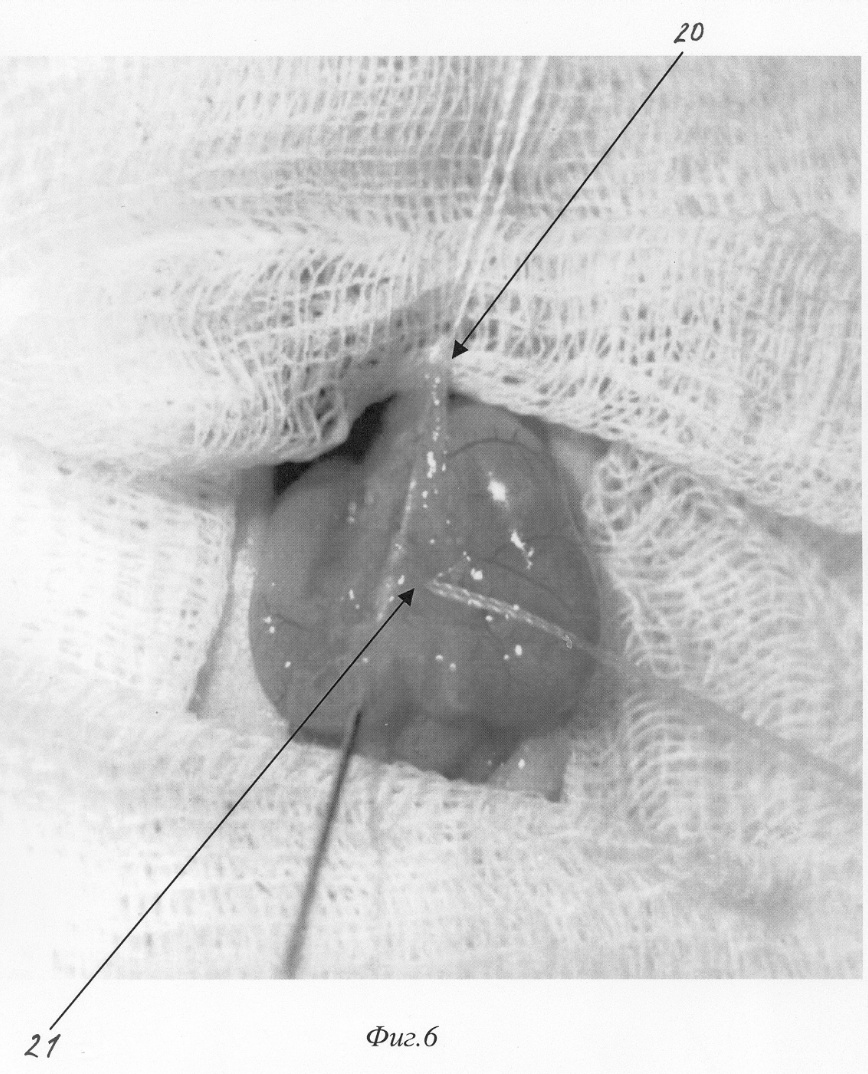

Изобретение относится к медицине, а именно к экспериментальной хирургии, и может быть использовано для моделирования острого деструктивного панкреатита у крыс. Близким решением является способ моделирования, разработанный Aho HJ, Koskensalo SM, и Nevalainen TJ, описанный в статье Experimental pancreatitis in the rat. Sodium taurocholate-induced acute haemorrhagic pancreatitis. Scand J Gastroenterol 15: 411-416, 1980. Который заключается в трансдуоденальной катетеризации общего желчного протока и введение таурохолата натрия (0,4 мл 4% раствора) в общий желчный проток и протоки поджелудочной железы. При использовании данного способа моделирования острого деструктивного панкреатита патогенетические механизмы, лежащие в основе большого количества летальных исходов, отличаются от таковых при развитии острого панкреатита в клинике. Так, таурохолат, являясь гемолитическим ядом, при применении в вышеуказанных концентрациях вызывает внутрисосудистый гемолиз. Другим отрицательным свойством данной модели является невозможность влияния на площадь панкреонекроза. Немаловажным фактором, влияющим на интрапанкреатическую активацию ферментов поджелудочной железы, является уровень рН в ее протоковой системе, что никак не учитывается в данной модели. Задачей изобретения является разработка модели острого панкреатита, наиболее оптимально соответствующей патогенетическим механизмам, имеющим место при развитии острого панкреатита у человека, позволяющей регулировать площадь панкреонекроза, а также снижение летальности, обусловленной гемолитическим действием вводимого в протоки раствора. Поставленная задача решаются тем, что для моделирования острого деструктивного панкреатита вместо раствора таурохолата натрия мы используем трансдуоденальное внутрипротоковое введение специальной буферной системы, содержащей соль желчной кислоты при оптимальной для интрапанкреатической активации ферментов рН. Для возможности управления площадью панкреонекроза мы используем различное наложение (дистальнее или проксимальнее места впадения добавочного протока поджелудочной железы в общий желчный проток) лигатуры, что обеспечивает развитие тотального или субтотального панкреонекроза. Изобретение поясняется фигурами: – на фиг.1 изображено строение протоковой системы крысы (1); – на фиг.2 изображено строение протоковой системы крысы (2); – на фиг.3 изображен первый этап моделирования (срединная лапаротомия); – на фиг.4 изображен второй этап моделирования (выведение органов в рану); – на фиг.5 изображен третий этап моделирования (пункция двенадцатиперстной кишки и катетеризация общего желчного протока); – на фиг.6 изображен пример наложения турникетов для воспроизведения субтотального панкреонекроза; – на фиг.7 изображен пример наложения турникетов для воспроизведения тотального панкреонекроза; – на фиг.8 изображен пятый этап моделирования – ушивание лапаротомной раны. Способ осуществляется следующим образом. Операция проводится с соблюдением правил асептики и антисептики под эфирным наркозом. После обработки операционного поля послойно вскрывается брюшная полость (верхнесрединная лапаротомия) на протяжении 2-3 см (фиг.3). Операционное поле отгораживается стерильными салфетками. При вскрытии брюшной полости в рану выводится петля двенадцатиперстной кишки (фиг.2. 12, фиг 4). В гепатодуоденальной связке определяется общий желчный проток крысы диаметром 0,3-0,5 мм (фиг.2. 11, фиг.4. 16 ). На расстоянии приблизительно 1,5 см от ворот печени (фиг.2. 10) в общий желчный проток по задней поверхности впадает главный панкреатический проток (фиг.2. 9), который собирает секрет от желудочной и селезеночной частей поджелудочной железы и имеет диаметр приблизительно около 0,2-0,3 мм, что лучше видно при рассечении связки аналоги lig. gastrocolicum и отведении желудка кверху (фиг.1). При этом мы увидим дистальную часть общего желчного протока (фиг.1. 2), впадающий в него главный панкреатический проток (фиг.1. 3), желудочную часть поджелудочной железы (фиг.1. 7), прилежащую к задней стенке желудка (фиг.1. 4), и селезеночную часть поджелудочной железы (фиг.1. 6), прилежащую к воротам селезенки (фиг.1. 5). Также при этом доступе можно увидеть и дуоденальную часть поджелудочной железы (фиг.1. 8), дренирующуюся дополнительным протоком (фиг.1. 1), который впадает в общий желчный проток по задней его поверхности на расстоянии около 0,5 см от места вхождения общего желчного протока в стенку двенадцатиперстной кишки. Место впадения дополнительного панкреатического протока в общий желчный проток можно увидеть и при выведении ДПК, как это показано на фиг.2. 19. Интрамуральный отдел общего желчного протока (фиг.2. 14) открывается в просвет ДПК, что можно увидеть через стенку кишки (фиг.2. 14, фиг.4. 17). Найдя место впадения общего желчного протока от него отступают около 0,5 см в этом месте производят пункцию двенадцатиперстной кишки зондом, диаметром 0,3 мм (фиг.5. 19), который через большой дуоденальный сосочек проводится в общий желчный проток до середины расстояния между местами впадения панкреатических протоков (фиг.5. 19). После этого на общий желчный проток накладывается два турникета. Один выше места впадения основного панкреатического протока (фиг.6. 20, фиг.7. 22), второй, в зависимости от того, какую форму панкреатита необходимо воспроизвести (тотальную или субтотальную), выше (фиг.6. 21) или ниже (фиг.7. 23) места впадения добавочного протока поджелудочной железы. Турникеты затягивают. В проток при помощи насоса для микроинфузий вводят 0,3 мл буфера (содержащего 0,3 г трис-гидроксиметил-аминометана и 0,6 г дезоксихолата натрия в 100 мл при рН 8,8) при скорости потока 0,07 мл в минуту. Турникеты с протоков снимают спустя минуту после прекращения введения буфера и удаляют катетер из протока. После создания модели органы погружаются в брюшную полость. Убираются отгораживающие салфетки. Брюшная полость послойно ушивается отдельными шелковыми швами (фиг.8). Рана обрабатывается раствором антисептика. Пример конкретного применения. Исследование проведено на 100 самках крыс линии Вистар массой 200 г. С целью подтверждения наличия острого деструктивного панкреатита производилось морфологическое исследование образцов поджелудочной железы на сроке 12 часов (как наиболее информативного срока). Образцы поджелудочной железы забирались, фиксировались в 10% растворе нормального формалина, обезвоживались, заливались в парафин, готовились парафиновые срезы, которые затем окрашивались гематоксилин-эозином. Также производилось исследование активности амилазы в сыворотке крови и перитонеальном экссудате амилокластическим методом со стойким крахмальным субстратом по Каравею. Кроме этого оценивалась летальность за первые сутки с момента моделирования. Полученные данные сравнивали с данным контрольной группы (интактные животные). Так, нормальные значения активности амилазы, вычисленные для нашей лаборатории, – 61,76 г/ч/л. После моделирования острого панкреатита описанным выше методом через 12 часов с момента моделирования активность амилазы сыворотки крови при тотальном панкреонекрозе достигает уровня 144,77±3,2 г/ч/л (р<0,01), а перитонеального экссудата 1237,36±7,4 г/ч/л (р<0,01) г/ч/л, при субтотальном панкреонекрозе 160,56±4,3 г/ч/л (р<0,01) и 1548,21±8,3 г/ч/л (р<0,01) – соответственно. При морфологическом исследовании получены следующие результаты: Макроскопическая картина при вскрытии брюшной полости и грудной клетки крысы после моделирования тотального панкреонекроза. При вскрытии в брюшной полости до 5 мл серозно-геморрагического выпота во всех отделах, гиперемия париетальной и висцеральной брюшины брыжейка тонкой кишки отечна, с множественными мелкими очагами стеатонекроза. Печень не увеличена, темно-вишневого цвета, поверхность ее гладкая, края долей заострены. Почки без видимой макроскопической патологии. Селезенка умеренно увеличена в размерах, темно-вишневого цвета. При вскрытии просвета желудка и ДПК определяются множественные мелкие (точечные) эрозии шоколадного цвета. Поджелудочная железа резко отечна с участками стеатонекроза размерами от 0,3 до 0,5 см в диаметре. В области желудочно-дуоденальной части имеются участки геморрагического панкреонекроза размерами до 0,3 см в диаметре. Отмечается отек забрюшинной клетчатки. При вскрытии грудной клетки определяется гиперемия плевры и небольшое количества светлого выпота. Поверхность легких гладкая, буроватого цвета с множественными точечными кровоизлияниями. Сердце без видимых макроскопических изменений. Морфологическое исследование поджелудочной железы (окраска гематоксилин-эозином увеличение 20 В дуоденальной части определяется зона тотального некроза с участками геморрагии, массивной нейтрофильно-макрофагальной инфильтрацией. Структура ацинусов не сохранена. В желудочной части имеет место крупноочаговый панкреонекроз с единичными участками геморрагии, клеточными структурами разрушенных панкреатоцитов, нейтрофильно-макрофагальной инфильтрацией. В зонах, удаленных от очагов некроза, структура ацинусов сохранена. В участках, примыкающих к зонам некроза, панкреатоциты имеют вакуолизированную цитоплазму, ядра неправильной формы. В селезеночной части определяются множественные центролобулярные некрозы. Имеется значительное количество ацинусов с сохраненной структурой, встречаются интактные островки Лангерганса. Макроскопическая картина при вскрытии брюшной полости и грудной клетки крысы после моделирования субтотального панкреонекроза. При вскрытии брюшной полости определяется до 3-4 мл серозно-геморрагического выпота. Париетальная и висцеральная брюшина гиперемирована во всех отделах. Брыжейка тонкой кишки отечна, с умеренным количеством мелких очагов стеатонекроза. Печень не увеличена, темно-вишневого цвета, поверхность ее гладкая, края долей заострены. На разрезе структура паренхемы не изменена, сосуды полнокровны. Селезенка умеренно увеличена в размерах, темно-вишневого цвета. Почки увеличены серовато-бурого цвета, на разрезе отчетливо просматривается кортикальный слой, темно-вишневого цвета с серым оттенком. При вскрытии просвета желудка и ДПК определяются множественные мелкие эрозии шоколадного цвета. Поджелудочная железа резко отечна с участками стеато и геморрагического панкреонекроза в желудочной части до 0,3 см в диаметре и участками стеатонекроза в парапанкреатической клетчатке. Дуоденальная часть железы отечна. При вскрытии грудной клетки определяется гиперемия плевры и небольшое количества светлого выпота. Поверхность легких гладкая, буроватого цвета с множественными точечными кровоизлияниями. Сердце без видимых макроскопических изменений. Морфологическое исследование поджелудочной железы (окраска гематоксилин-эозином увеличение 20 В дуоденальной части определяется интерстициальный отек с геморрагическим пропитыванием. Структура ацинусов сохранена. В желудочной части имеет место крупноочаговый панкреонекроз с единичными участками геморрагий, клеточными структурами разрушенных панкреатоцитов, нейтрофильно-макрофагальной инфильтрацией. В зонах, удаленных от очагов некроза, структура ацинусов сохранена. В участках, примыкающих к зонам некроза, панкреатоциты имеют вакуолизированную цитоплазму, ядра неправильной формы. В селезеночной части определяются множественные центролобулярные некрозы. Имеется значительное количество ацинусов с сохраненной структурой, встречаются интактные островки Лангерганса. При моделировании острого панкреатита летальность к первым суткам составила 80,6% при тотальном панкреонекрозе и 56,3% при субтотальном панкреонекрозе. В образцах крови, взятых при тотальном и при субтотальном панкреонекрозе, гемолиза не выявлено. Таким образом, поставленная задача достигнута, во первых, за счет уменьшения количества желчной кислоты в водимом в протоки растворе, во вторых, за счет поддержания рН вводимого раствора на оптимальном для активации ферментов уровне, в третьих, за счет наложения турникета до или после места впадения дополнительного протока поджелудочной железы в общий желчный проток и управления площадью некроза. В результате применения данного способа моделирования острого панкреатита развивается крупноочаговый некроз поджелудочной железы (тотальный или субтотальный), что, в свою очередь, приводит к: 1. Выявлению достоверных признаков развития острого панкреатита (морфологических и биохимических). 2. Возможности управления площадью некроза. 3. Снижению уровня летальности, связанной с гемолитическим действием солей желчных кислот. Формула изобретения